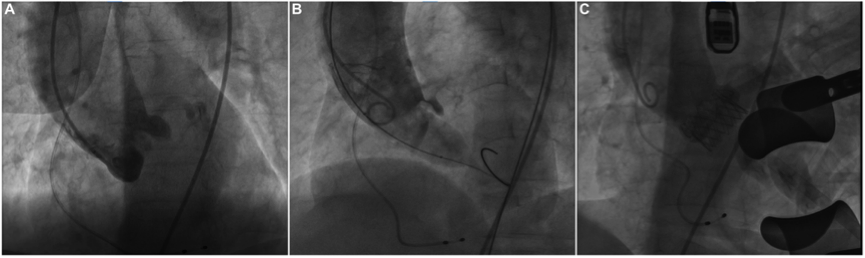

手术在TAVR混合手术室进行。TAVR手术开始时,术中透视下双侧冠状动脉通畅(图2A)。常规进行球囊预扩张以评估环上结构,并使用23mm×40mm Z-Med™球囊根据环周长衍生的直径评估冠状动脉闭塞的风险。出乎意料的是,球囊扩张后,右冠状动脉不可见,LMA中的血流减少(图2B),表明RCA完全闭塞,LMA被原生左冠状动脉瓣叶部分闭塞。患者的血氧饱和度从100%急剧下降到72%。术中经胸超声心动图显示球囊放气后的瓣膜梯度为20 mmHg。因此,多学科小组决定暂停该程序。对患者的解剖结构进行了仔细和全面的重新评估,出于安全考虑,计划使用J-Valve瓣膜进行经心尖TAVR。

随后,3天后在全麻下进行带J-Valve瓣膜的经心尖TAVR。引入并反复调整23 mm J-Valve瓣膜系统,以确保三个持握器正确放置在左、右和非冠状窦中,并准确围绕原生小叶。人工瓣膜在快速心室起搏下定位于主动脉瓣环下方1 cm后逐渐释放。手术进展顺利,最终的透视显示了人工瓣膜的正确位置和双侧冠状动脉的通畅情况(图2C)。最终超声心动图显示瓣膜周围轻度渗漏,残余跨瓣梯度为3 mmHg。患者出院时无明显心力衰竭症状,出院后可轻松开展日常活动。在30天的随访中,患者心功能NYHA II级,超声心动图显示主动脉瓣功能正常,跨瓣平均梯度为5 mmHg。

图2. 术中透视。(A)透视显示球囊预扩张前双侧冠状动脉畅通。(B)在球囊扩张期间,右冠状动脉不可见,左冠状动脉血流减少。(C)透视显示J -Valve瓣膜展开后双侧冠状动脉通畅